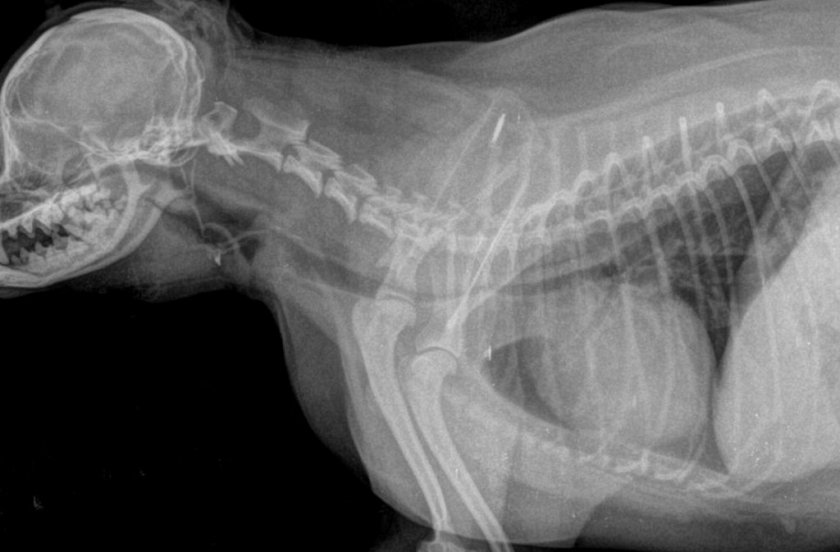

Поэтому для точного определения наличия и стадии развития стеноза дыхательных путей назначаются специальные обследования:

- рентгенография шейного отдела (в момент вдоха) и грудного отдела (в момент выдоха) сбоку;

- рентгеноскопия (считается более информативным методом по сравнению с рентгенографией, поскольку позволяет увидеть положение трахеи в динамике, в процессе дыхания;